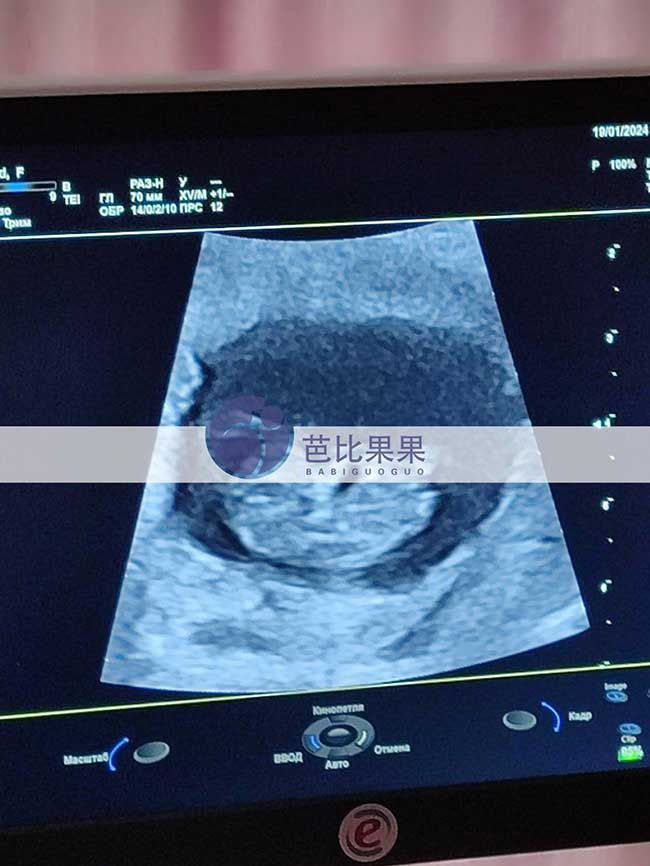

D先生夫妻在格鲁吉亚移植的乌克兰试管妈妈来医院做B超检查

D先生夫妻在格鲁吉亚助孕的乌克兰试管妈妈来医院做B超检查,胎宝宝发育的很好,感谢试管妈妈